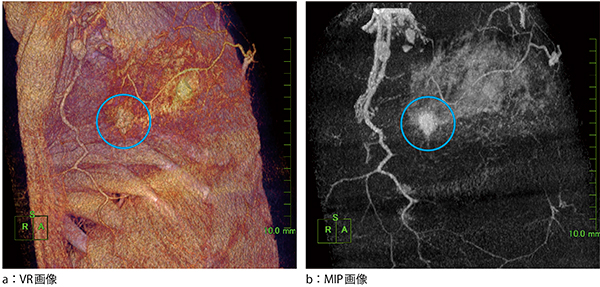

症例1は浸潤性乳管がんの症例である。この症例は,複雑な構造のカラーマップのみを当てたVR画像(図2 a)でも視認できるが,MIP画像(図2 b)を用いると明瞭に描出される。

図2 症例1:浸潤性乳管がん

VR画像と比較し,MIP画像では腫瘍の輪郭が明瞭に描出される。